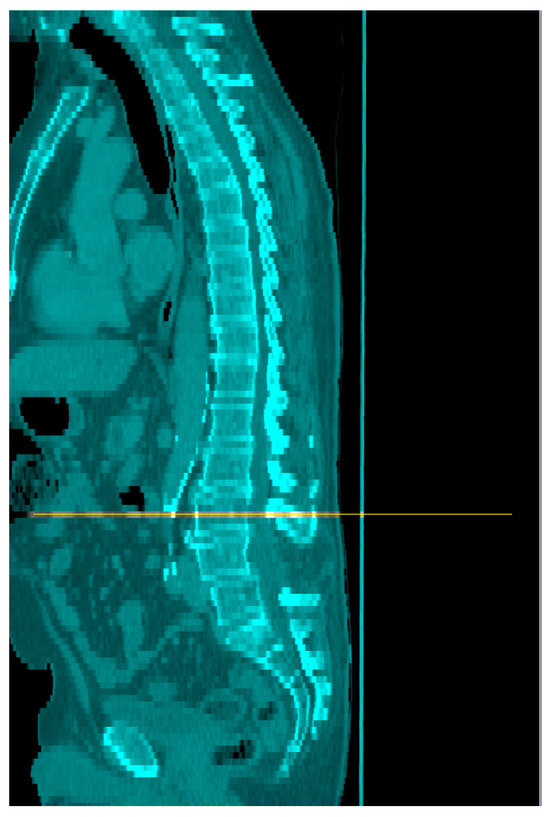

- Tomovision. Slice-0-matic Alberta Protocol Users Manual. 2017. Available online: https://tomovision.com/Sarcopenia_Help/index.htm (accessed on 11 February 2024).

- Byrne, C.A.; Zhang, Y.; Fantuzzi, G.; Geesey, T.; Shah, P.; Gomez, S.L. Validation of skeletal muscle and adipose tissue measurements using a fully automated body composition analysis neural network versus a semi-automatic reference program with human correction in patients with lung cancer. Heliyon 2022, 8, e12536. [Google Scholar] [CrossRef]